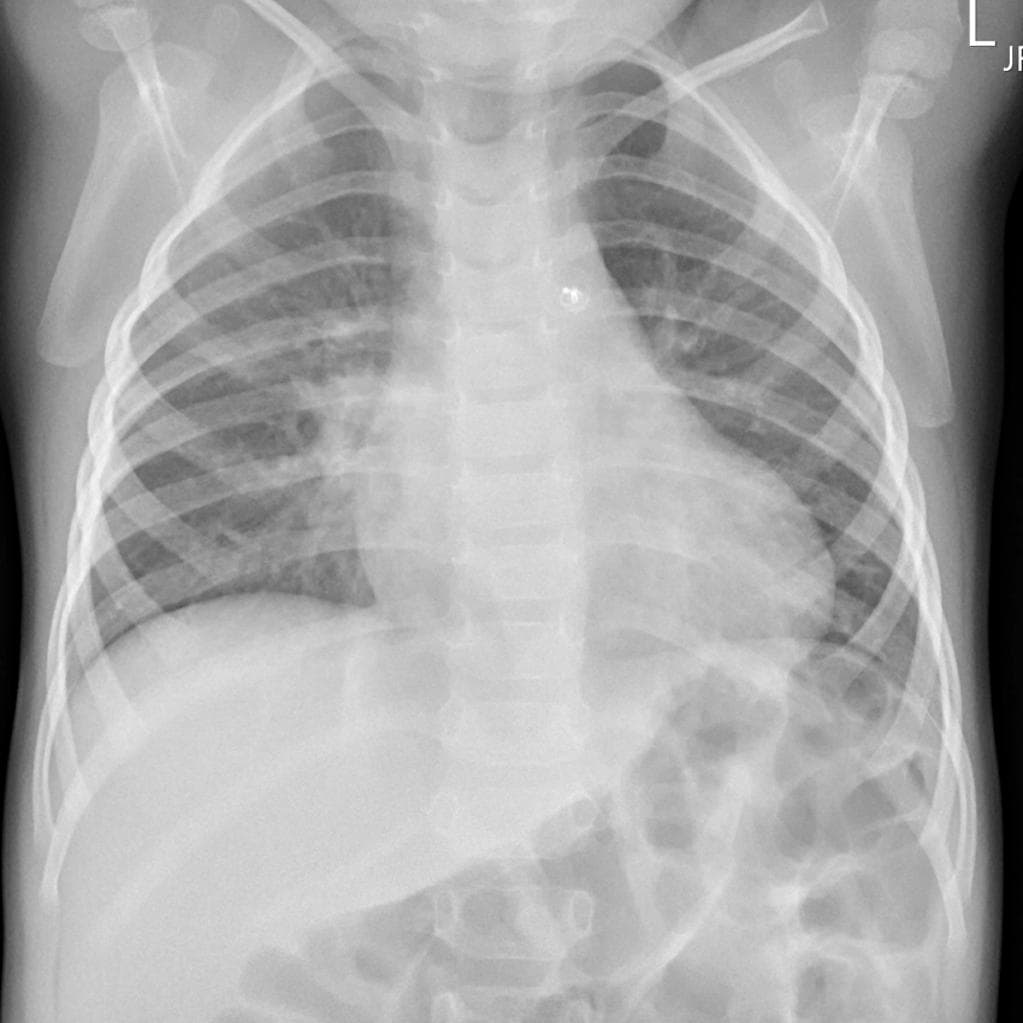

Ca bệnhU nhầy nhĩ trái (Left atrial myxoma)

U nhầy nhĩ trái (Left atrial myxoma)

- Đã biết khối choán chỗ nhĩ trái (known left atrial mass).

- Khối choán chỗ nhĩ trái (left atrial mass) giàu mạch máu (vascularized), kích thước 4,6 cm, không cuống (sessile), giới hạn rõ (well defined).

- Kết quả giải phẫu bệnh cuối cùng là u nhầy (myxoma).